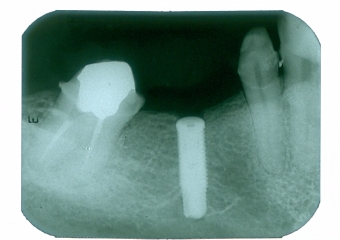

Raio X do implante

Raio X com prótese fixa em porcelana sobre implante Cone Morse